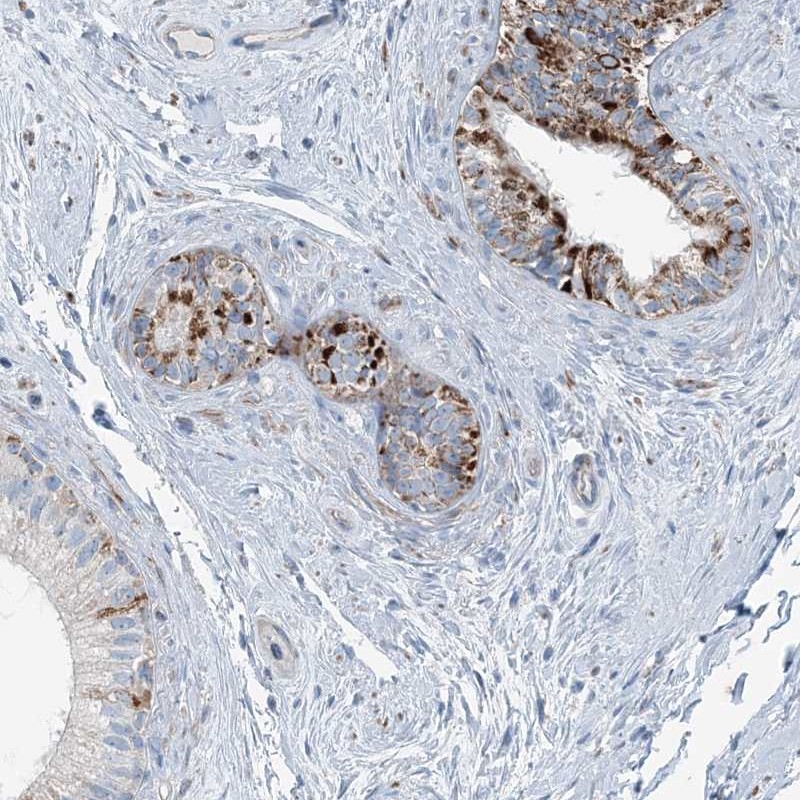

Immunohistochemistry analysis in human epididymis and pancreas tissues using Anti-INTU antibody. Corresponding INTU RNA-seq data are presented for the same tissues.